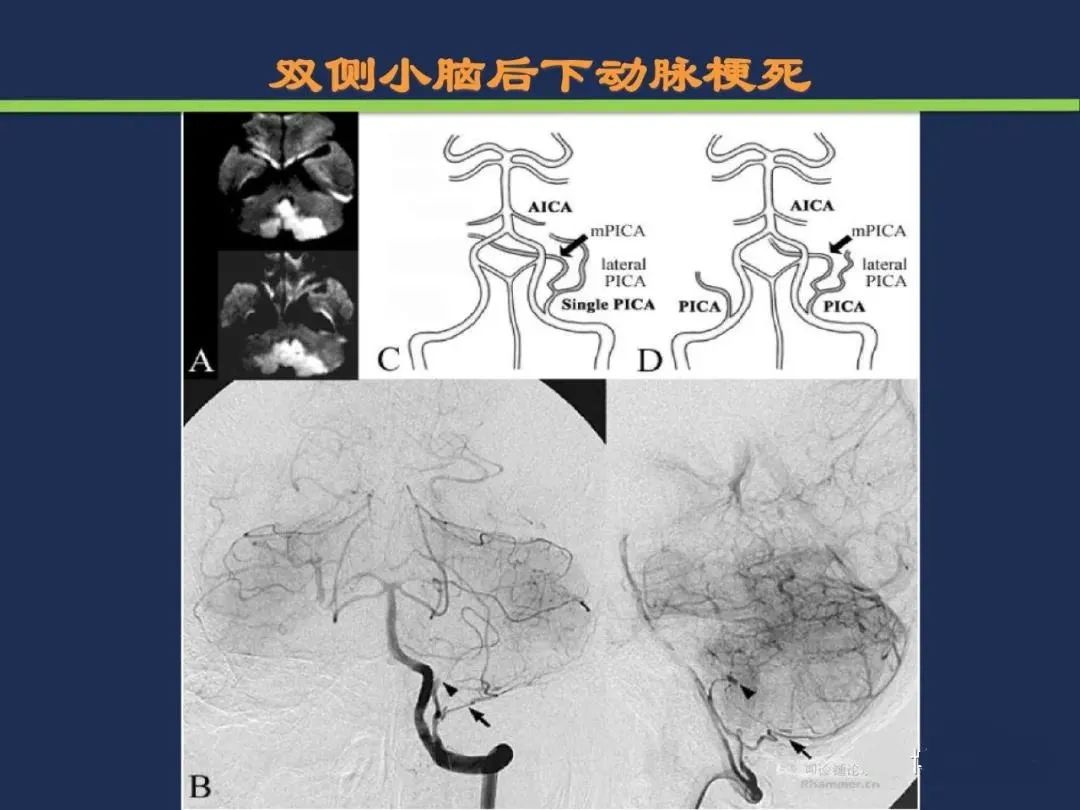

小脑后下动脉